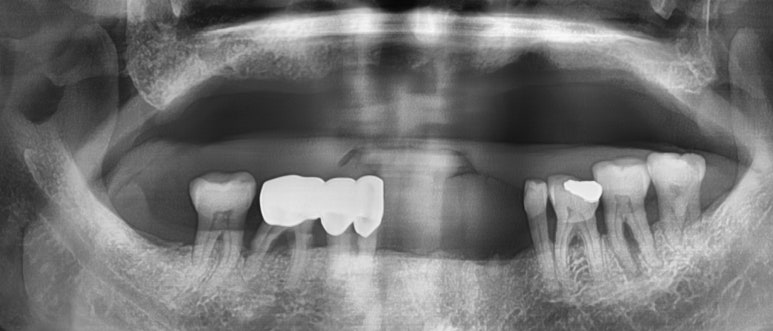

틀니를 빼면 위 사진과 같은 상태였고요

엑스레이에서 보듯이 이가 많이 없으셨죠.